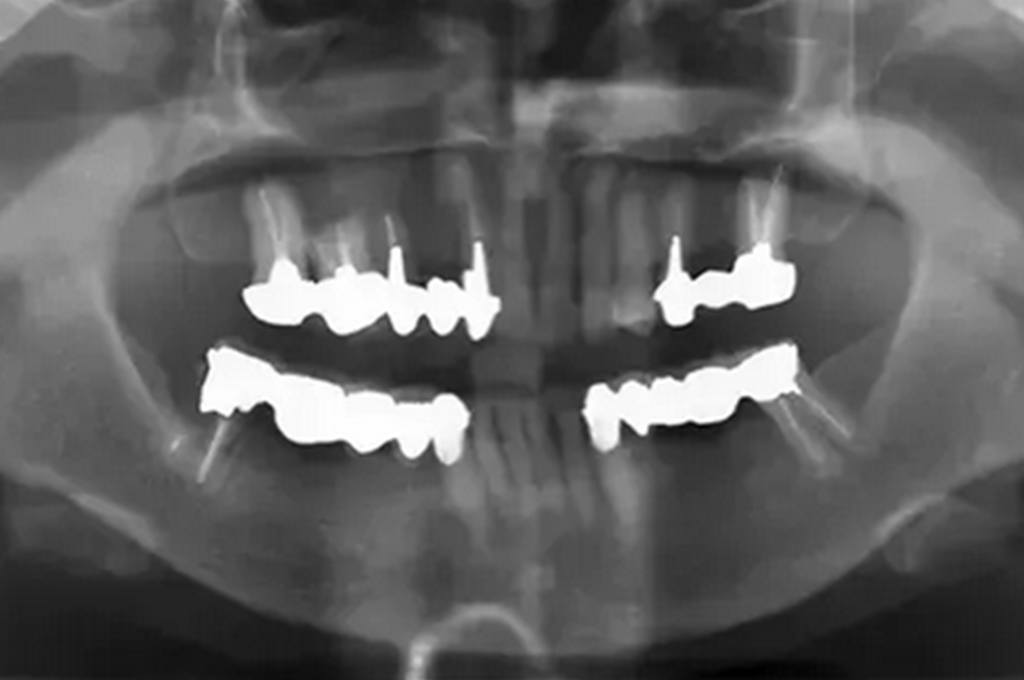

治療前に行ったレントゲンです。ブリッジを支える歯が虫歯になってしまい、しっかり噛めなくなってしまいました。